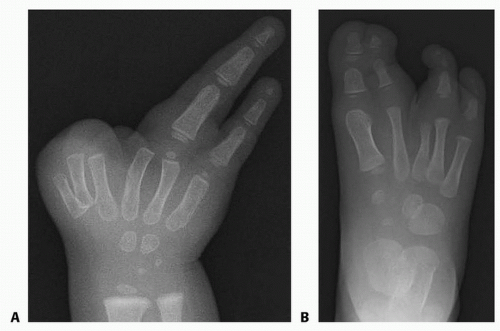

FIG 2 • This 3-year-old patient with typical cleft hand/cleft foot syndrome (the example case throughout) has two ulnar fingers but no thumb (A), as well as webbed great and second toes (B).

Physical examination of the hand (FIG 2A)

Physical examination of the foot (FIG 2B)

FIG 3 • Radiography of the example case shows three metacarpals on the radial side of the hand (A) and separate skeletal structures in the foot despite webbing of the great and second toes (B). Note that there are only two phalanges in the second toe. The epiphysis of the second metatarsal is not present in this early radiograph, but it is distally located in subsequent films (see TECH FIG 7A), indicating that this is indeed a phylogenetic second toe rather than a preaxial synpolydactyly.

Plain radiographs of the hand and foot are required (FIG 3).